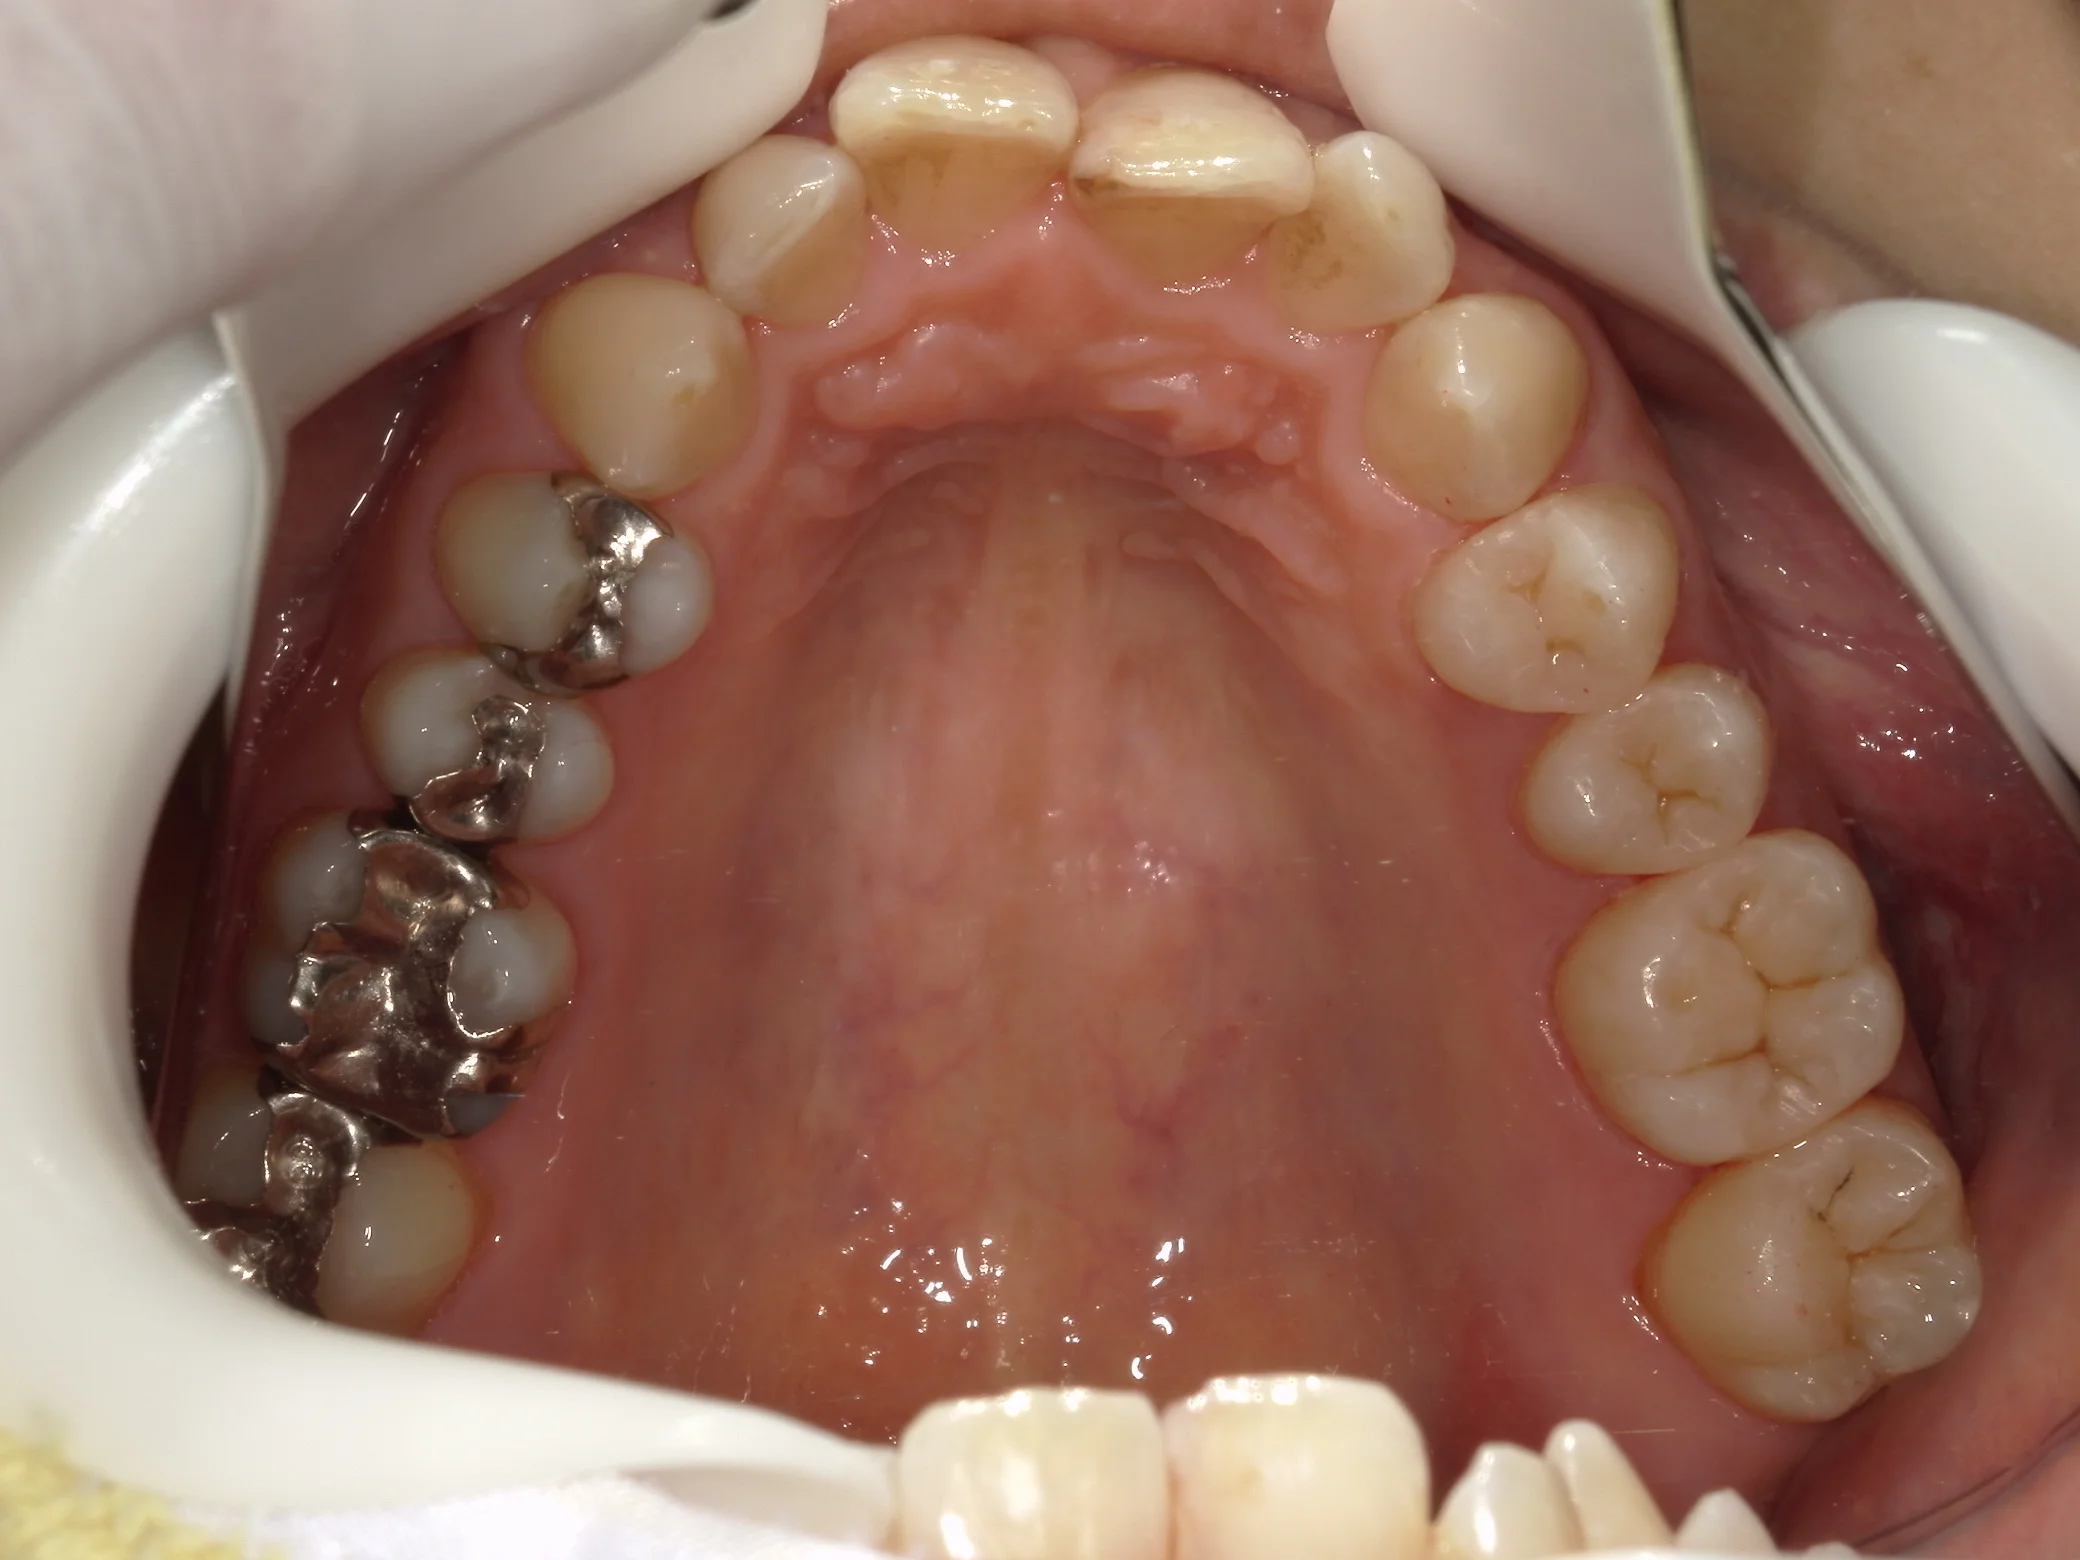

そして詰め終わったのがこちらです。

基本的には噛み合わせの調整は最小になるように行うべきですが、少し多めに調整することになってしまいました。

そして、別アングルからの写真がこちらです。

こちらが、術前。

こちらが術後。

随分と自然な感じに仕上げることが出来たと思います!